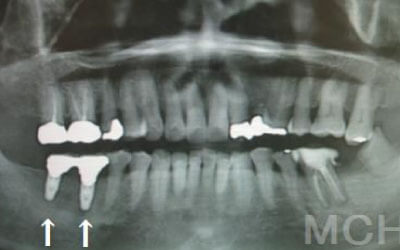

骨が薄い場合、そのままインプラントを行うのはお勧めできません。

ただし、事前に骨を増やす治療を行ったり、インプラントと同時に骨を増やす治療を施したりすることで、インプラントは可能です。

1)インプラント治療を行う前に、骨の治療が必要かもしれません。

2)骨の治療から始めると、その分、治療期間が長くなります。

3)骨の治療は、通常のインプラント治療よりも難易度が高いため、経験の豊富な先生やインプラント認定医のいる歯科医院で治療を受けることをお勧めします。

4)骨の状況をしっかり把握するためにも、CT撮影が必須となります。